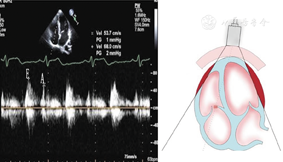

(1)胸骨旁左心室长轴切面(图1图2图3)

胸骨旁左心室长轴切面引导2a区M型超声心动图,显示收缩末期和舒张末期室间隔厚度、左心室内径和左心室后壁厚度测量方法